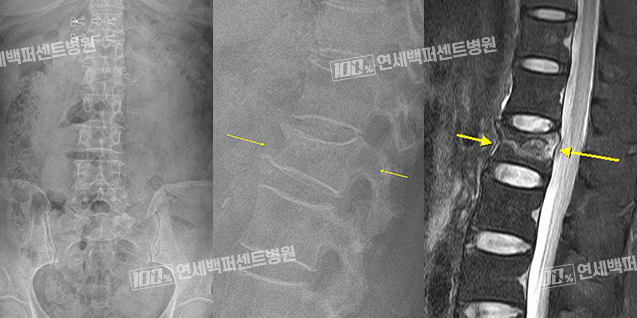

척추압박골절 치료 Before & After

치료 전

척추성형술 치료 후